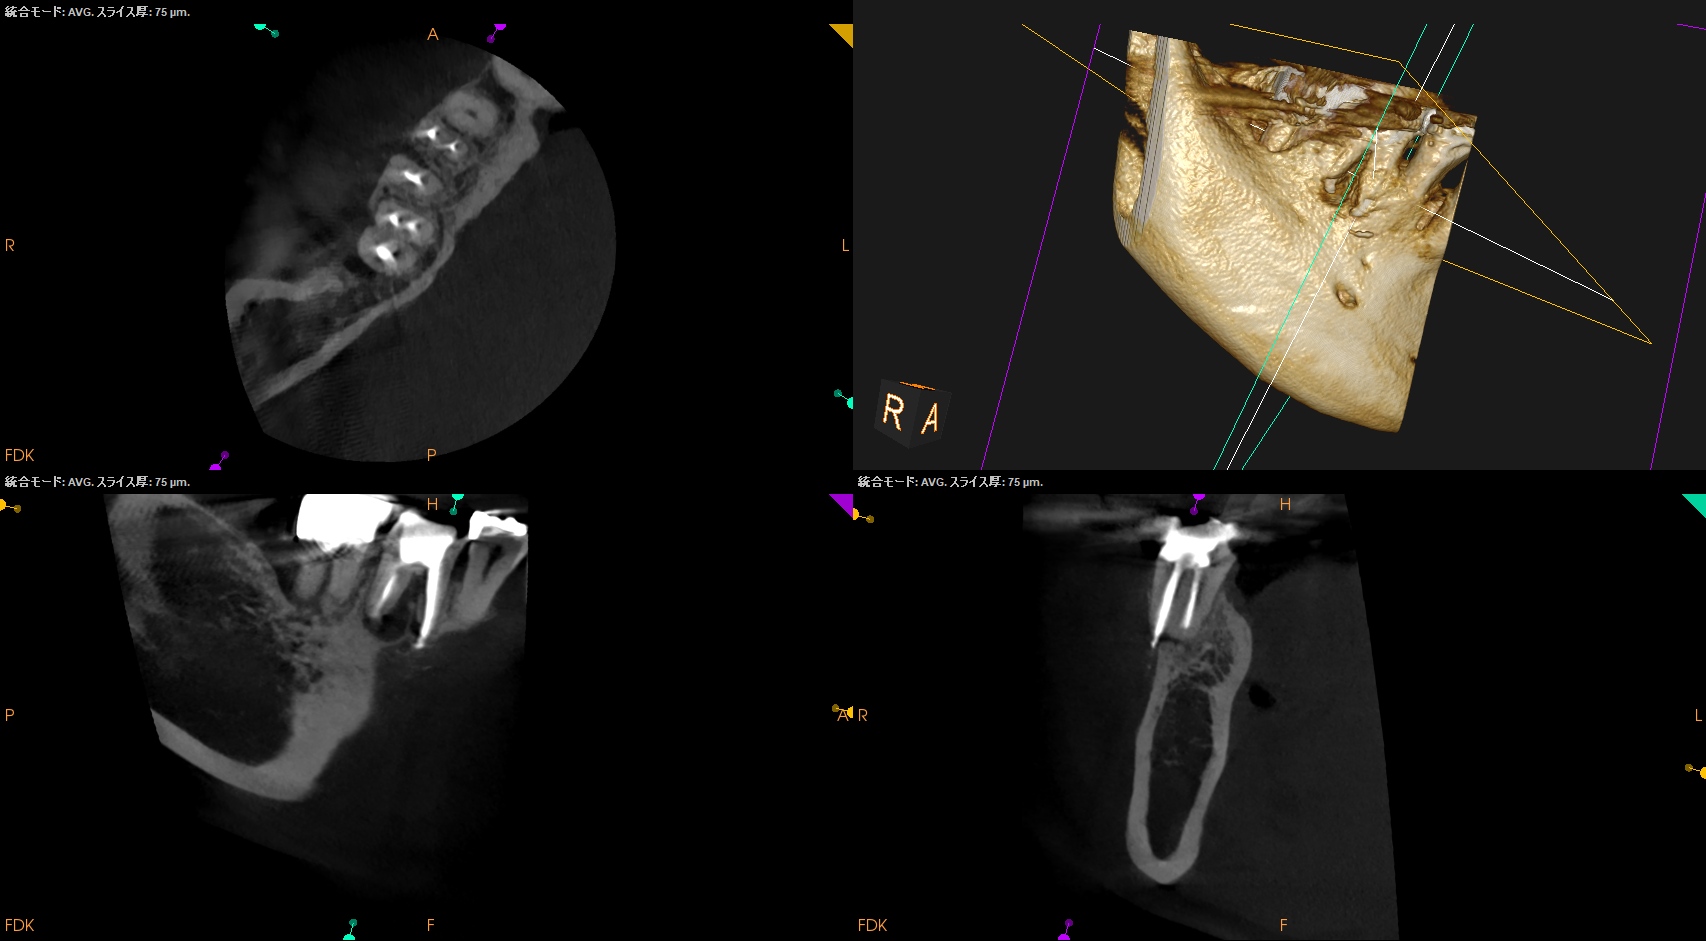

術後にPA, CBCTを撮影した。

#30

MB

ML

D